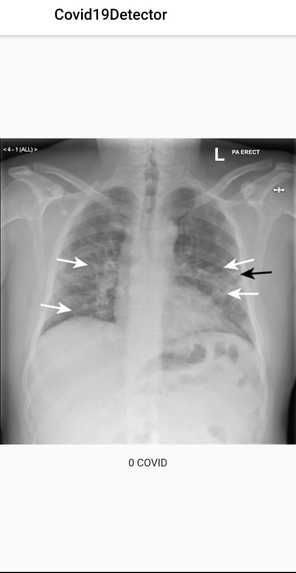

1-Covid detection through lung x-ray using a Kaggle dataset and embedding in the flutter app through Tensorflow.